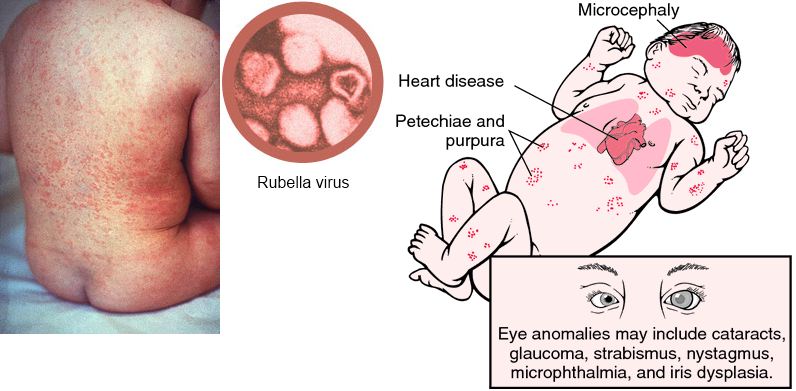

Rubella

“German Measles”, virus

“German Measles”, virus- Symptoms: low grade fever, tender lymph nodes, rash on face that spreads down body

- Complications: in pregnant women causes Congenital Rubella Syndrome (CRS), born with growth and mental retardation, heart defects, eye defects (such as cataracts), deafness, liver, spleen and bone marrow complications.

- Death/Statistics: 20% chance of damage to the fetus if a mother is infected early in pregnancy. During the 1962-1965 global rubella pandemic, an estimated 12.5 million rubella cases occurred in the United States, resulting in 2,000 cases of encephalitis, 11,250 therapeutic or spontaneous abortions, 2,100 neonatal deaths, and 20,000 infants born with CRS.

- Although Rubella has been eliminated in the United States, it is endemic in the rest of the world, responsible for an estimated 100,000 infants born with Congenital Rubella Syndrome each year.